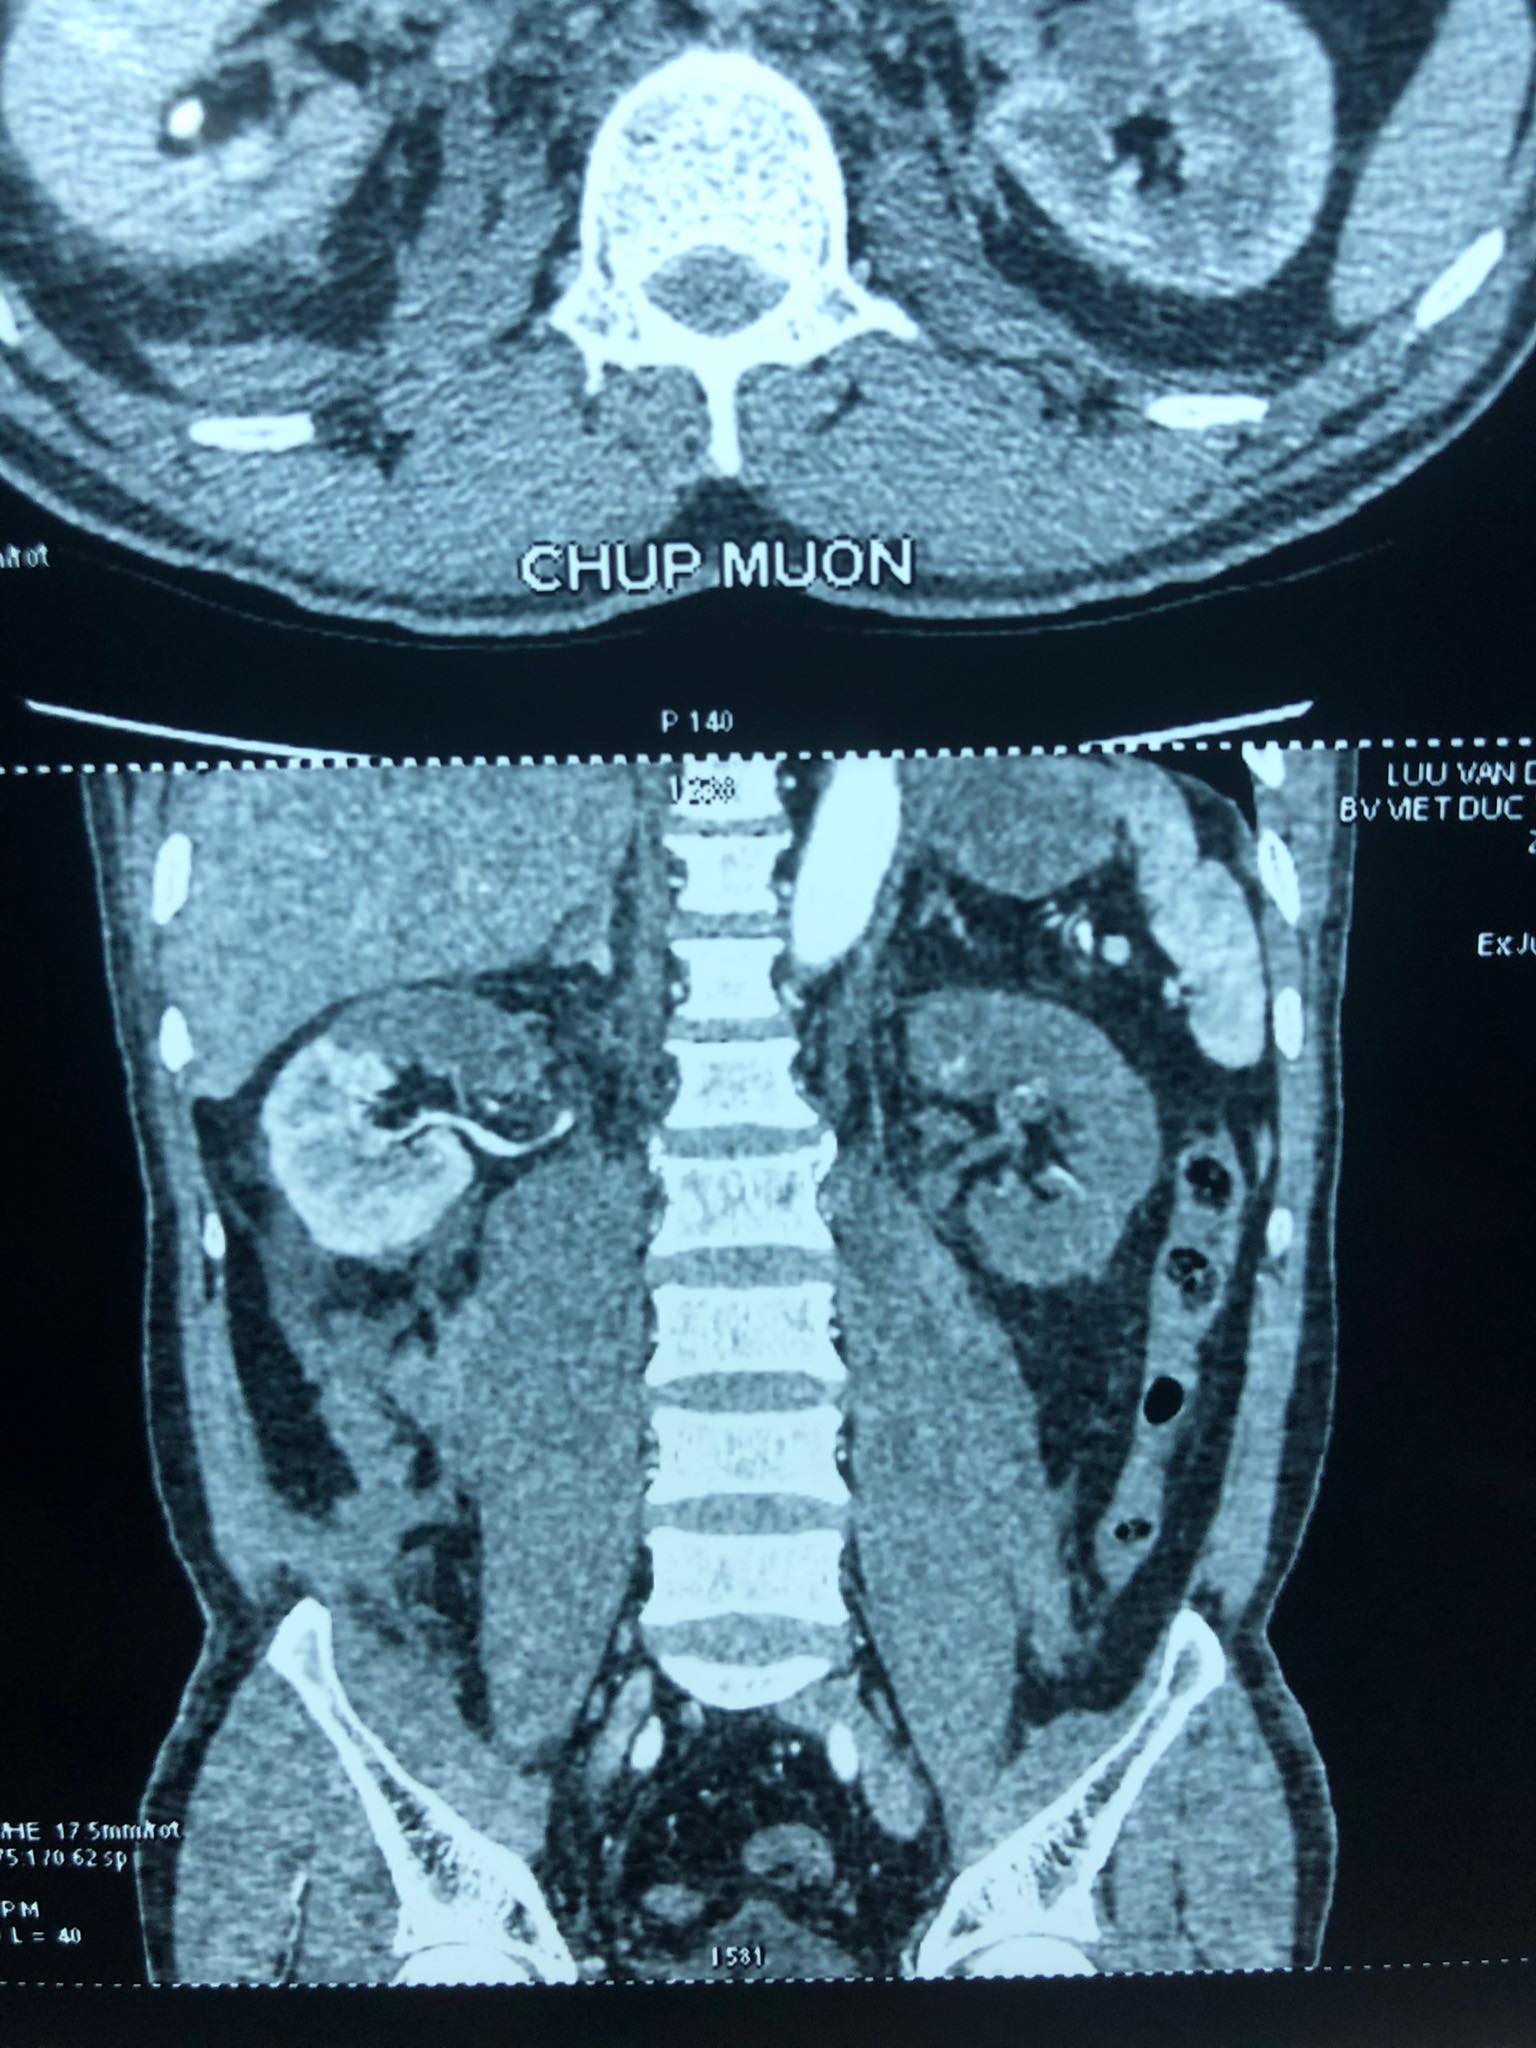

QĐND Online – Chiều 20-7, Bệnh viện Hữu nghị Việt Đức cho biết, bệnh viện vừa ghép thận tự thân thành công cứu nam thanh niên tai nạn xe máy tắc động mạch thận giờ thứ 24.